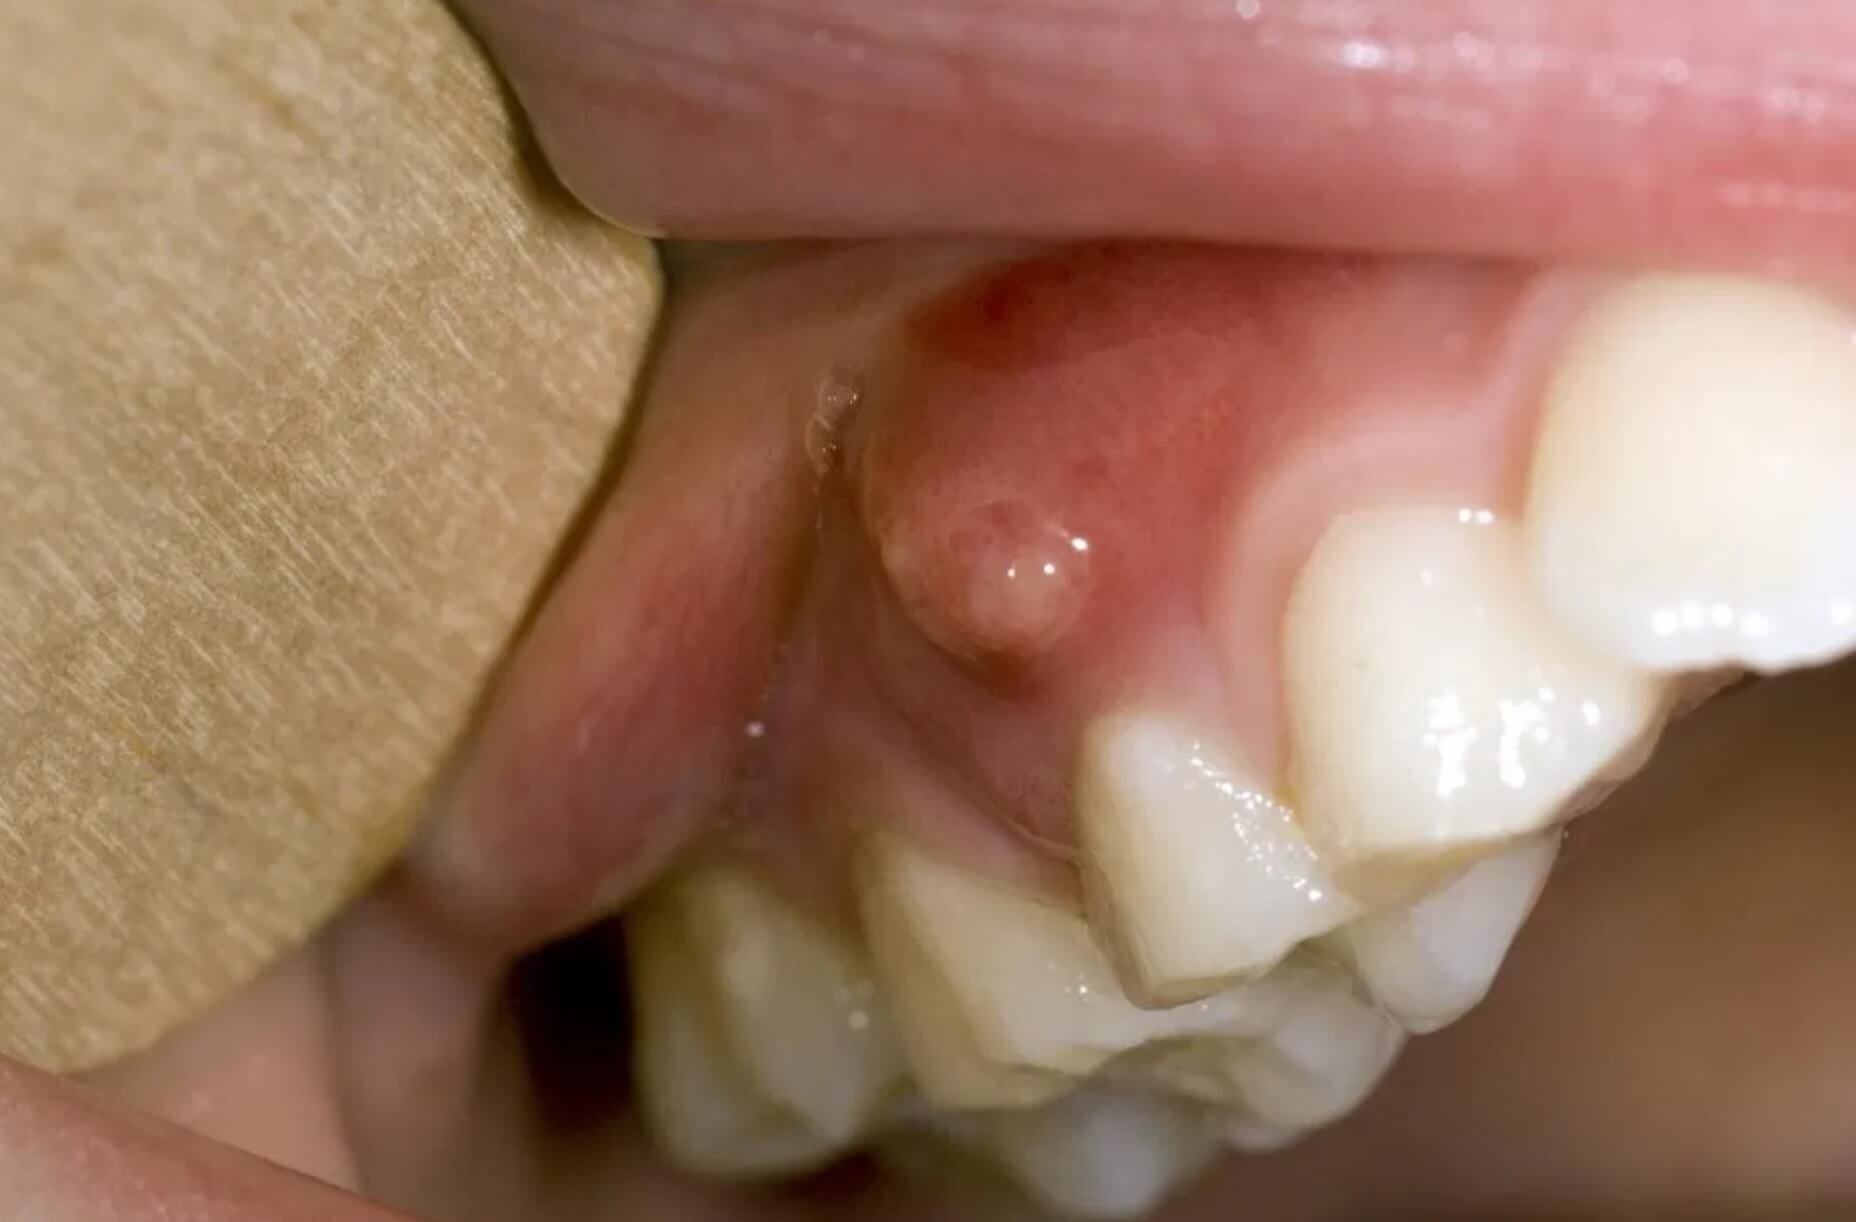

Gingival fistula: what is it and how is it treated?

Gingival fistula is an asymptomatic pathology, it is a lesion of the gingiva due to an oral cavity infection.

At its appearance the gingival fistula is a localized lesion of the gingiva, but if it is not treated with specific therapies it can extend to neighboring tissues and also affect the teeth, endangering the stability of the same.